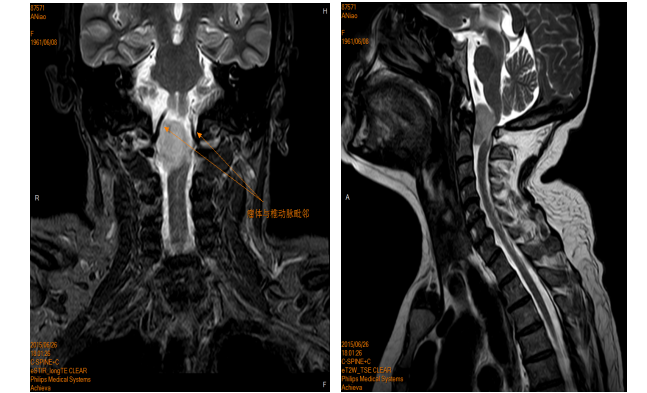

患者阿某,患有枕颈部肿瘤,四肢肌力因肿瘤压迫而下降至3级,日常生活能力受到严重影响。尽管在其省内多家医院寻求治疗,但由于病情复杂,多家医院均拒收并建议其前往北京等大城市寻求更高水平的医疗援助。

然而,患者因家庭经济条件困难,无法承受长途跋涉和高昂的医疗费用,在绝望时找到米明珊教授。

经过米明珊专家团队的详细检查和诊断,确诊为枕颈部肿瘤,并力排众议,与家属进行深入沟通后进行手术。

颈椎管和枕颈部的结构复杂,肿瘤生长部位邻近呼吸生命中枢,与周围组织的粘连较重,手术风险难度可想而知,米明珊专家团队克服了重重困难,经过4小时25分钟的紧张的显微镜下手术,成功将肿瘤全部切除。出血仅有350ml。

▲原肿瘤已切除,解除压迫

术后,患者在医护人员的精心照料下,经历了25天的康复期,重新学会了站立,成功地从病房迈步前行。家属们激动得热泪盈眶,他们紧紧握住医生的手,不停地道谢。

枕颈部肿瘤切除手术一直被视为医学领域的一大难题,米明珊专家团队用自己的智慧和勇气,为患者开辟了一条新的生命之路。